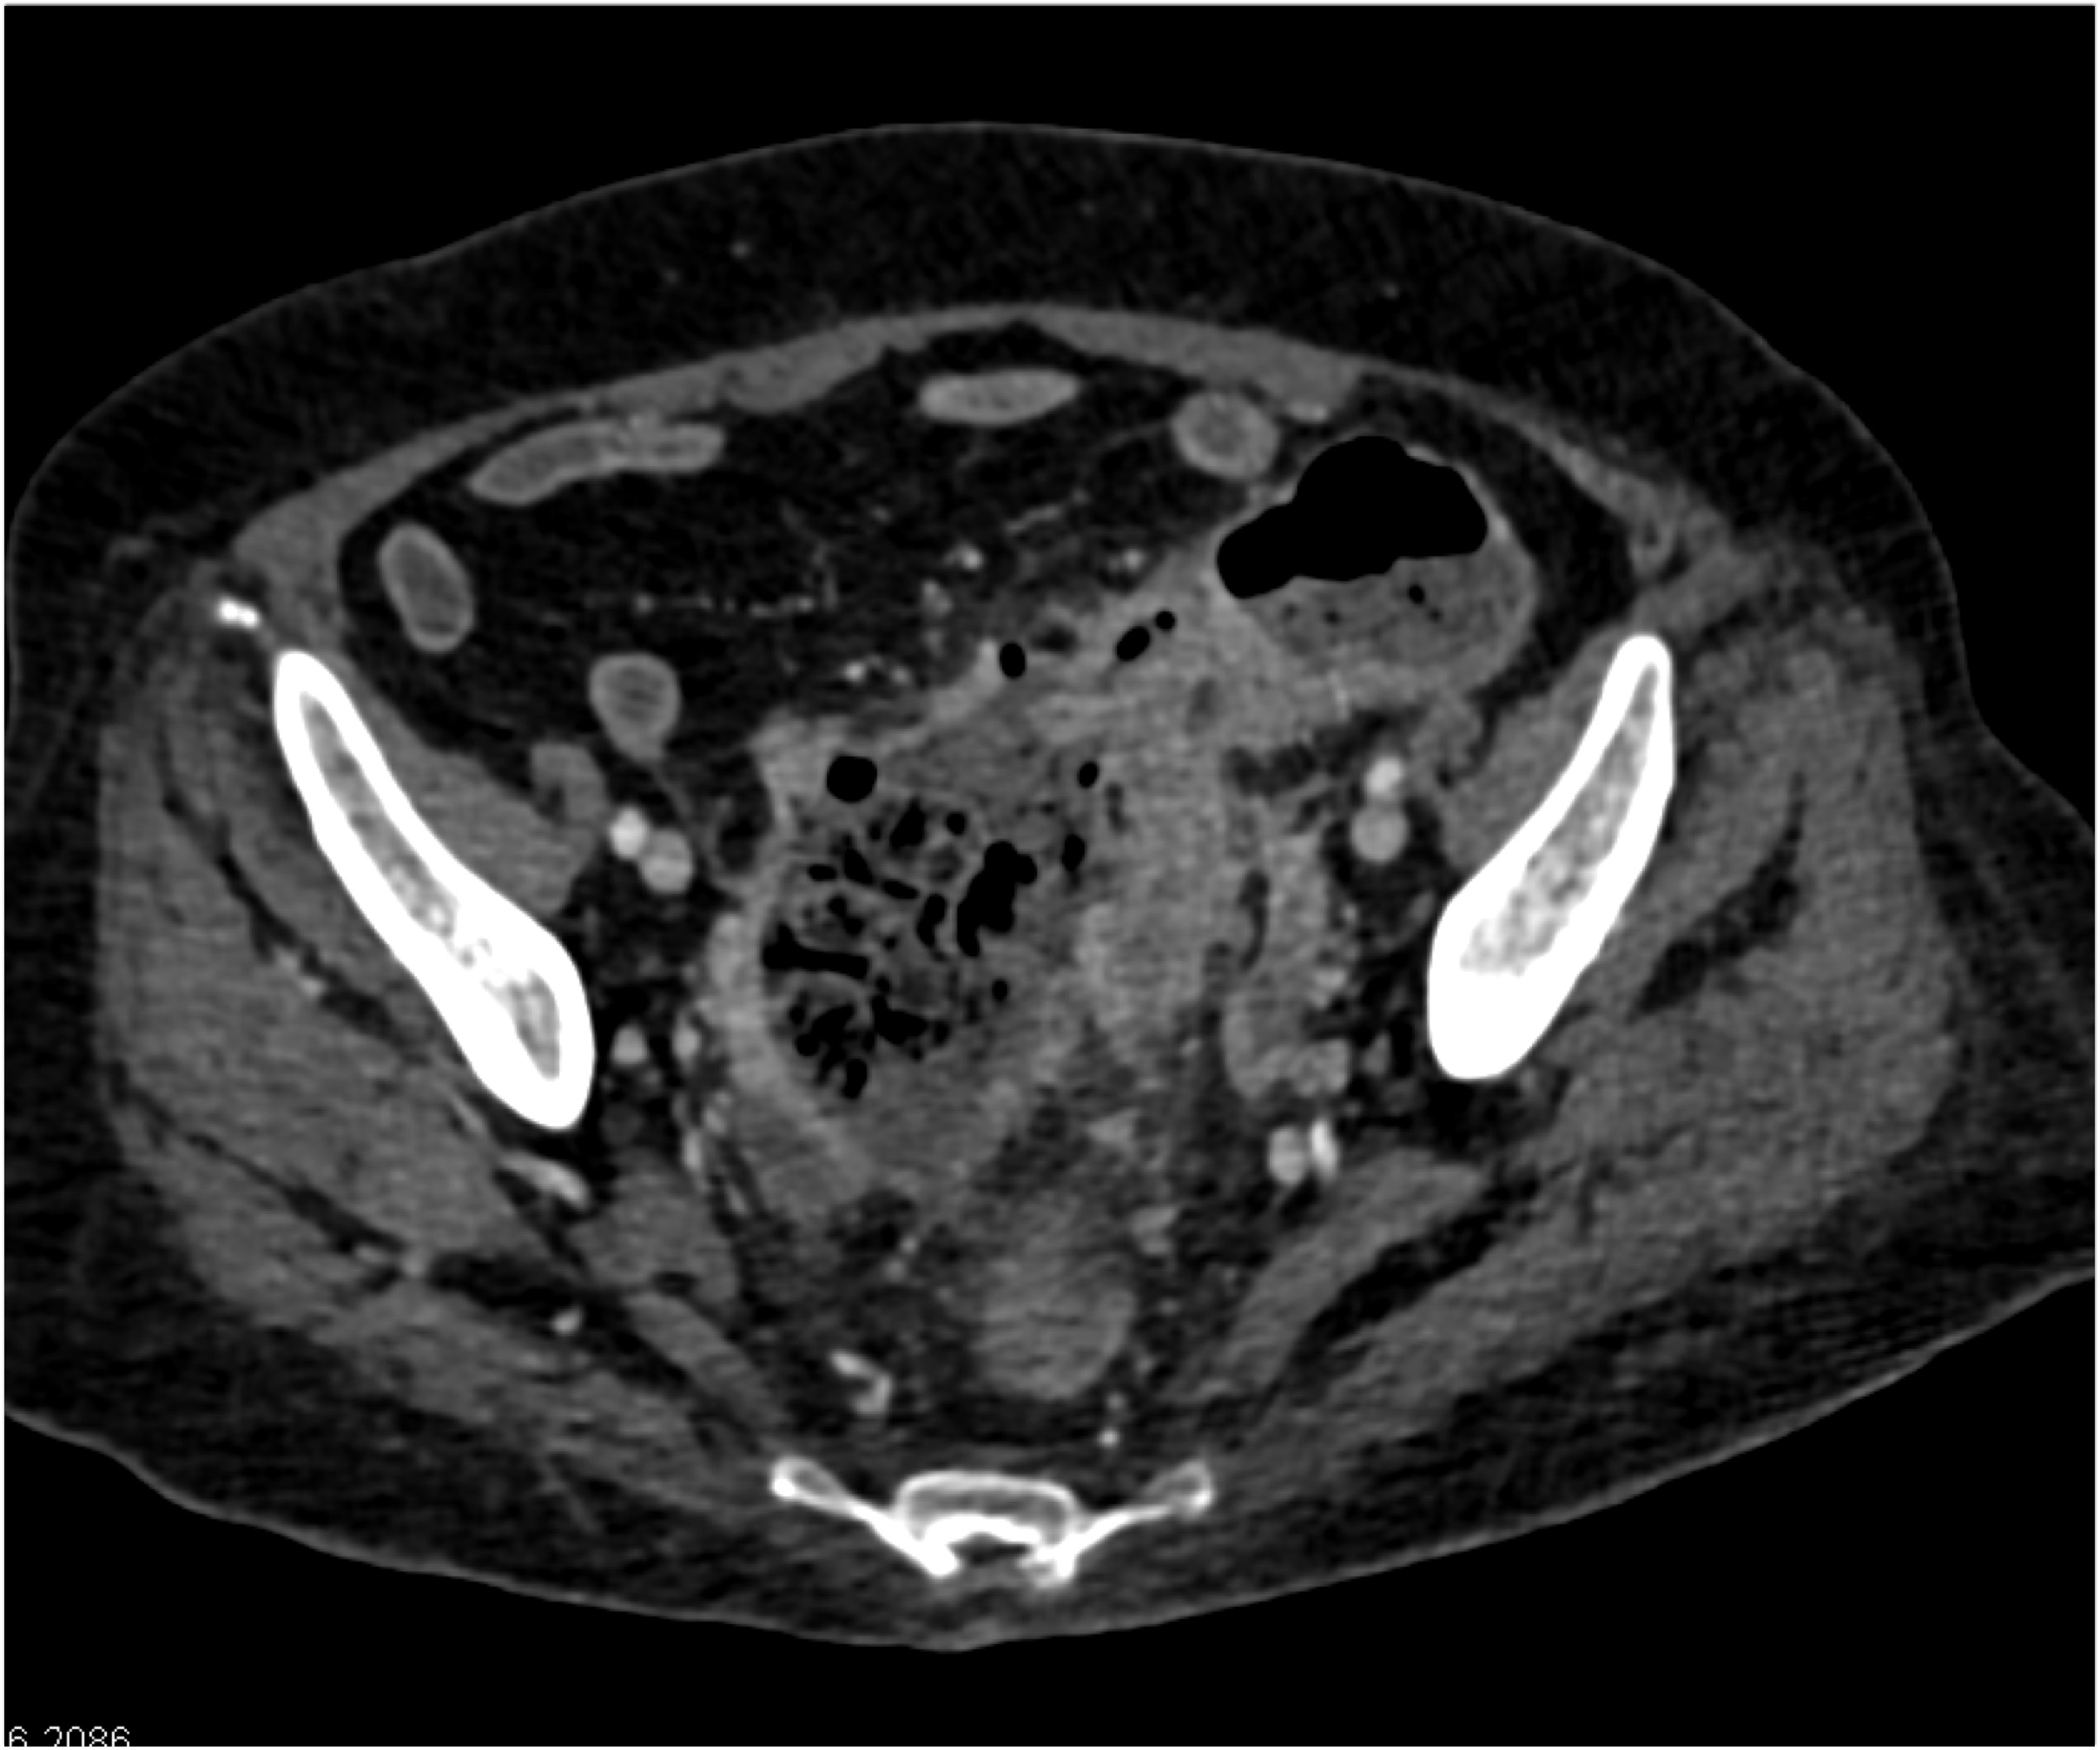

6) In this patient with LUQ pain and sepsis the best dx is?

gastric emphysema

gastritis

gastric ulcer

lymphoma